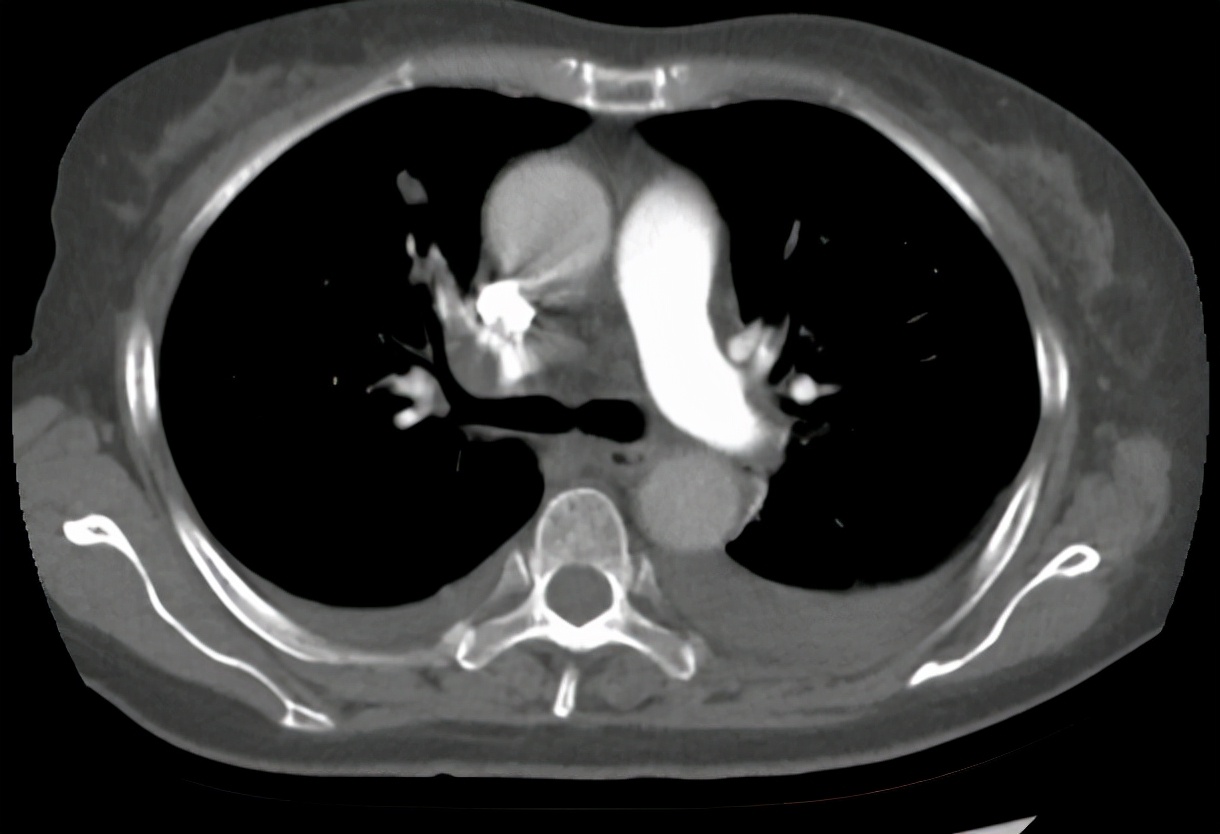

放疗结束后3个月,患者出现胸闷气促,氧饱和度降落,至我科再次就诊,2020-12-23肺动脉CTA:双肺肺动脉多发栓塞。双肺炎症考虑;附见:双侧胸腔积液。考虑患者疾病进展,出现胸腔积液,肺栓塞严重威胁生命,予吸氧、抗凝、化痰、抗感染、营养支持治疗。期间腹胀明显,腹围较前也增大了,肝功能及胆红素进一步升高,考虑有腹水及胆道梗阻可能, 2021-1-6 全腹部CT:胰腺恶性肿瘤化疗后改变,肝脏第二肝门区占位,网膜多发结节灶,考虑转移瘤,建议随诊增强复查。低位性胆道梗阻伴肝内、外胆管明显扩张,胆囊内胆汁淤积。大量腹盆腔积液。予腹腔穿刺引流、护肝、降胆红素治疗,效果不佳,患者精神越来越差,患者想要回家见亲戚朋友最后一面,选择自动出院。

2020-12-23肺动脉CTA